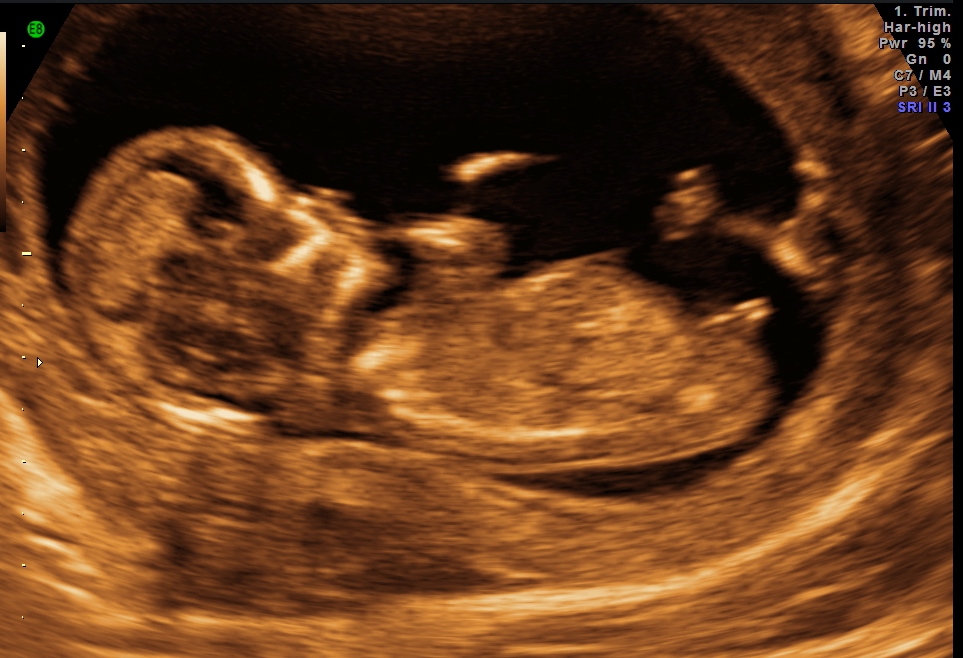

This is my scan at 12+2weeks. What do you think?

Boy! :)

Nub looks boy, skull looks girl! What are you hoping for? Good luck.

I think the nub looks like a boy!

Im gonna be an opposite and guess girl:), I just think babies bum has the slightest curve to it and the actual shape of it looks girly, wouldnt be suprised to be wrong though with that iffy angle lol:)